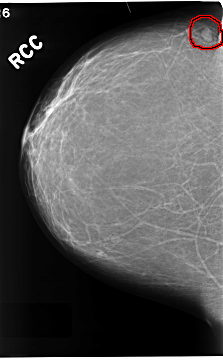

C_0210_1.RIGHT_CC

FILE: C_0210_1.RIGHT_CC.OVERLAY

TOTAL_ABNORMALITIES 1

ABNORMALITY 1

LESION_TYPE MASS SHAPE OVAL MARGINS CIRCUMSCRIBED

ASSESSMENT 3

SUBTLETY 5

PATHOLOGY BENIGN

TOTAL_OUTLINES 1

BOUNDARY